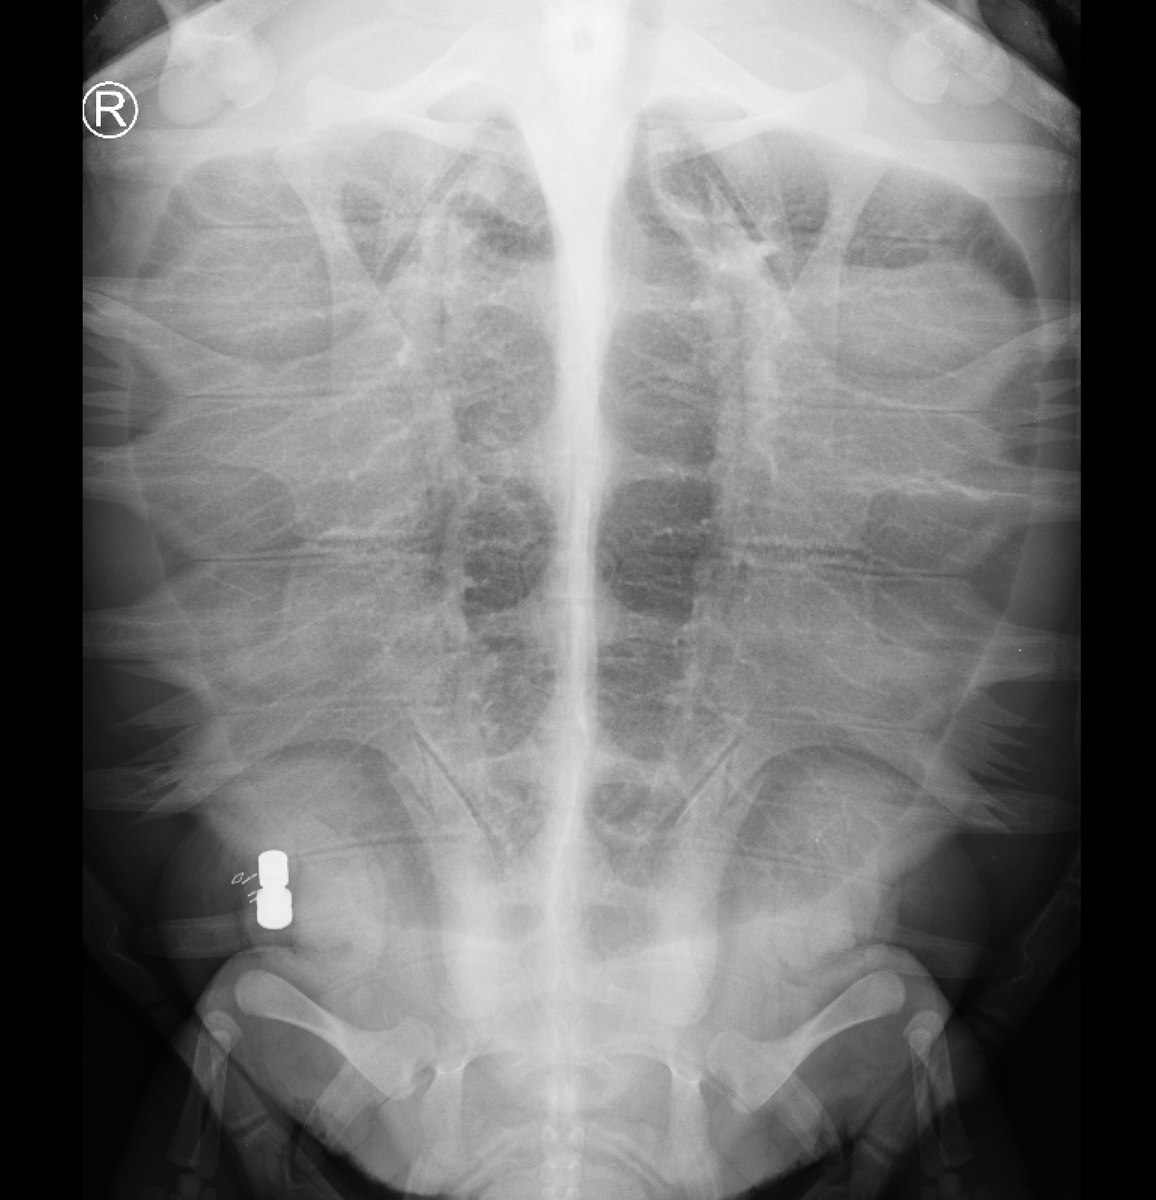

Below is an X-ray of one of our released #Loggerhead sea turtles, which depicts a surgically implanted #AcousticTag. We released three rehabilitated sea turtles back into the wild w/ these acoustic tags. Now, we are retrieving the data from them. More: https://t.co/tCaZHZJVBb